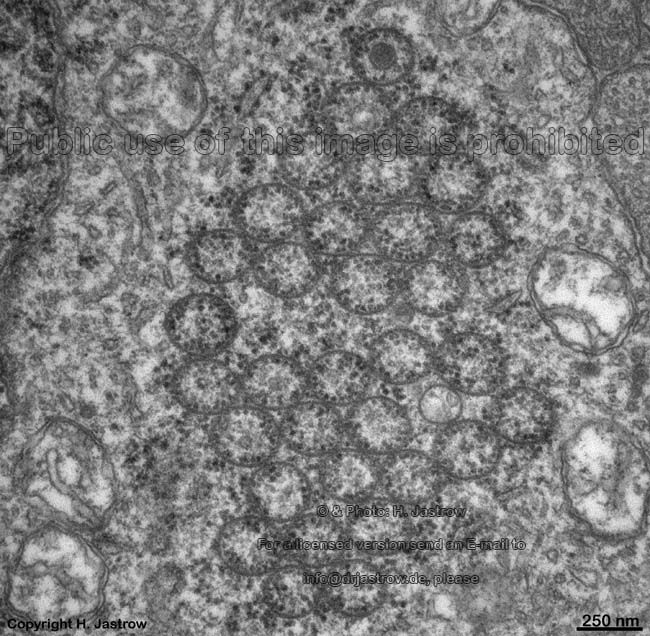

Overview aggregated macrotubules (Macrotubuli aggregati; MA):

All images were taken from horizontal cells of human retina.

cross-sectioned

MA 1

MA 2

Macrotubuli aggregati (MA; English: aggregated macrotubules) are known as Kolmer`s crystalloids, a not quite correct term derived from light microscopy. They are grouped large tubes running almost parallel to each other. Their walls consist of obliquely running parallel intermediate filaments (diameter: 12.5 nm). They have simple, single layered walls in over 97%. However, few of them show double or multiple layered walls. Large amounts of ribosomes are attached mainly to the inner walls of the tubes via fine stalks. The mean diameter of the tubes is 235.7 ± 29.7 nm. Their length may reach over 10 µm. MA are present in about 20% of all horizontal cells in human retina. They could not be detected in other species investigated so far with few exceptions: rhesus monkey, chimpanzee, beagle dogs. Further MA were noted in pathological human cornea and in the pinealocytes of one mouse species (Acomys cahirinus dimidiatus). Probably they support the cytoskeleton and serve as storage site for ribosomes, however their function still remains to be elucidated.